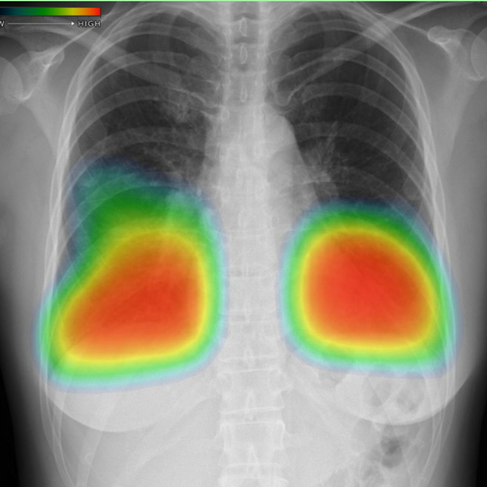

最近の特徴的な画像(右側は、AIによる胸部レントゲンの画像評価結果です。非常に優秀です)を共有します。

インフルエンザ肺炎

マイコプラズマ肺炎

細菌性肺炎